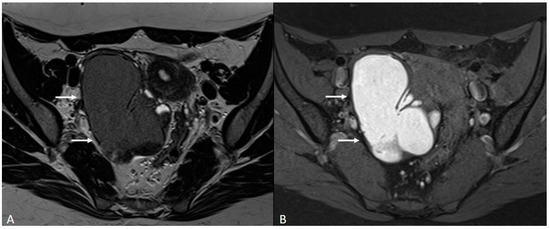

In this paragraph, we will explore the main signs in post-operative imaging in order to provide the radiologist with an indication to evaluate MRIs of women with extensive and complex endometriosis undergoing surgery (Figure 15 and Figure 16).

Figure 15.

Para-uterine fluid collection in a 43-year-old female who underwent several gynecological surgeries for deep infiltrative endometriosis. (A) Axial T2WI. Compartmentalized hyperintense collection in the left para-uterine area after pelvic surgery (white arrow). (B) Coronal T2WI. Endometriotic localization of the vescico-uterine pouch (black arrow).

Figure 16.

Localization of endometriosis in the left parametrium and ureteral stenosis in 49-year-old female who underwent supracervical hysterectomy, bilateral salpingectomy and mild vaginal bleeding and abdominal pain. (A) Axial T2WI; (B) Sagittal T2WI. Endometriotic localization of the left parametrium (white arrow), with irregular margins and heterogeneous signal intensity. Tractions towards the sigmoid colon, left pararectal fascia, anterior pelvic peritoneal reflection and adnexa. Ureteral stenosis caused by the parametrial plaque (dotted arrows in (B)). (C) Axial T2WI; (D) Axial fat-suppressed T1WI. Endometriotic nodule of the left pelvic wall (white arrow).

One of the main challenges for the radiologist is to make a correct differential diagnosis between post-operative fibrosis and recurring/residual disease.

MRI can highlight the difference between these two conditions: fibrotic scars or plaques appear as bands of hypointensity on T2WI, without areas of cystic degeneration, blood foci (hyperintense in T1WI) or even nodular thickenings that are otherwise typical signs of endometriotic lesions [89].